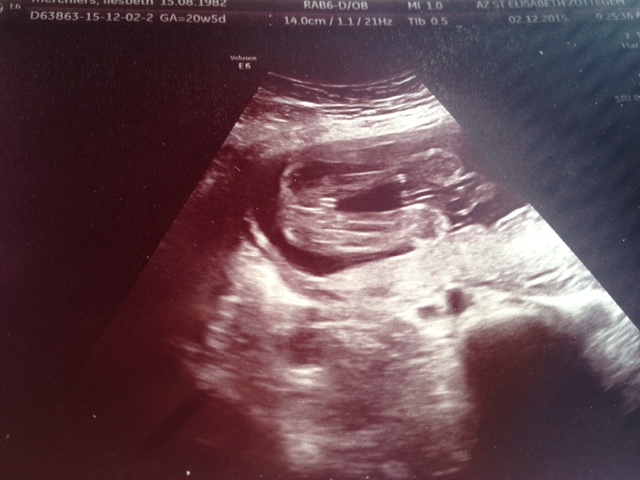

Boy or girl? Your guesses please?